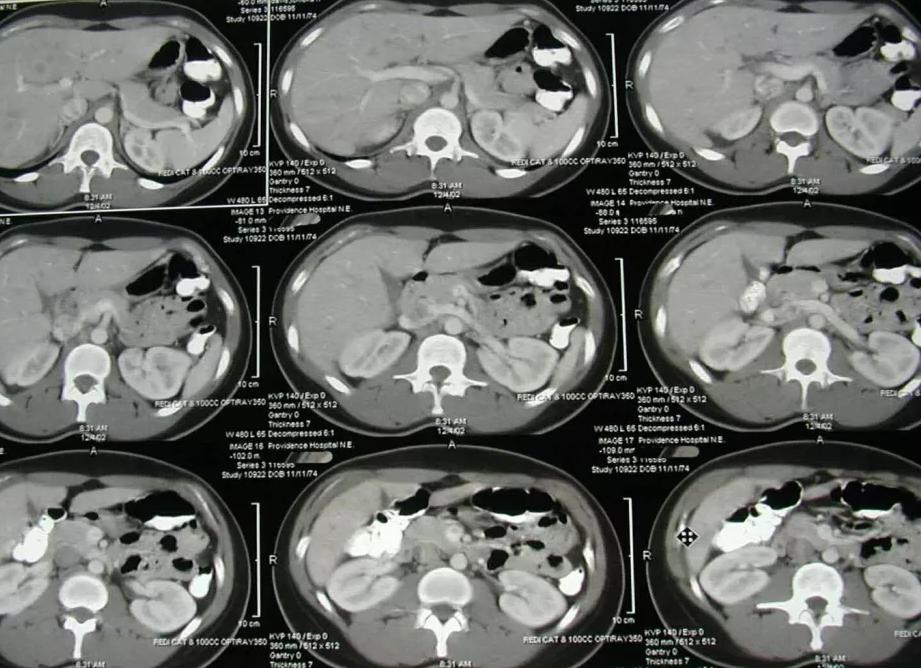

Компьютерная томография головы является одним из самых популярных способов диагностики, применяемых в современной медицине. С его помощью можно получить полное представление о состоянии здоровья головного мозга, а также прилегающих костных структур и мягких тканей. Как проходит такое сканирование, и что оно показывает, в каких ситуациях назначается врачом, а каким пациентам противопоказано – ответы на эти вопросы вы найдёте в представленной ниже статье. Также мы сообщим о мерах предварительной подготовки и о болезнях, которые может обнаружить этот метод. Также предоставим вам информацию об альтернативных методах диагностики, о преимуществах КТ и томографии с контрастом.